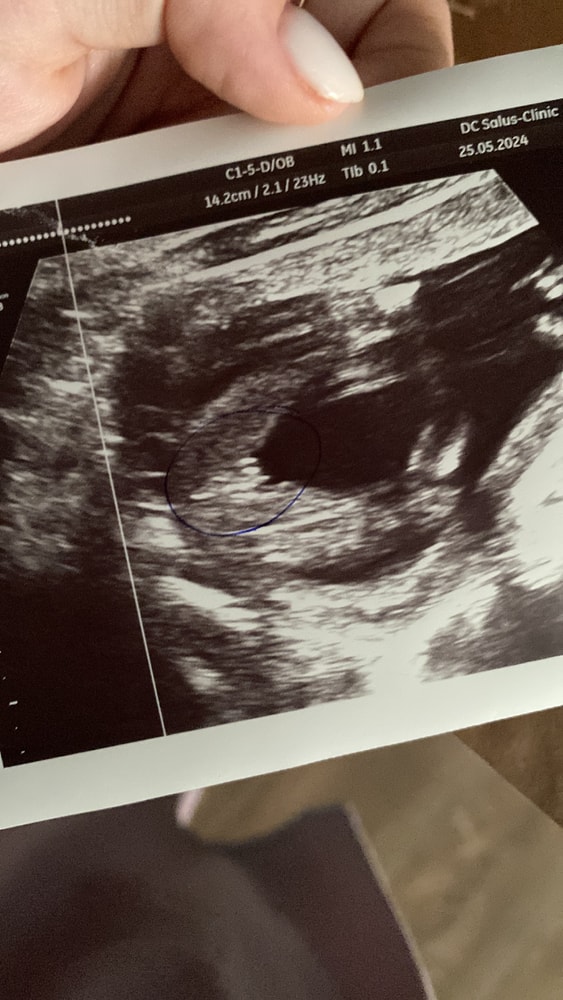

D.S, собственно да, должен быть. Сейчас уже с дочкой и не найду той фотки где там прям как машонка была, без кранчика я сомневалась до последнего, что это девочка, только в роддоме уже перед родами меня заверили, что там дама. Поэтому я бы еще разок проверила недельки через 3.